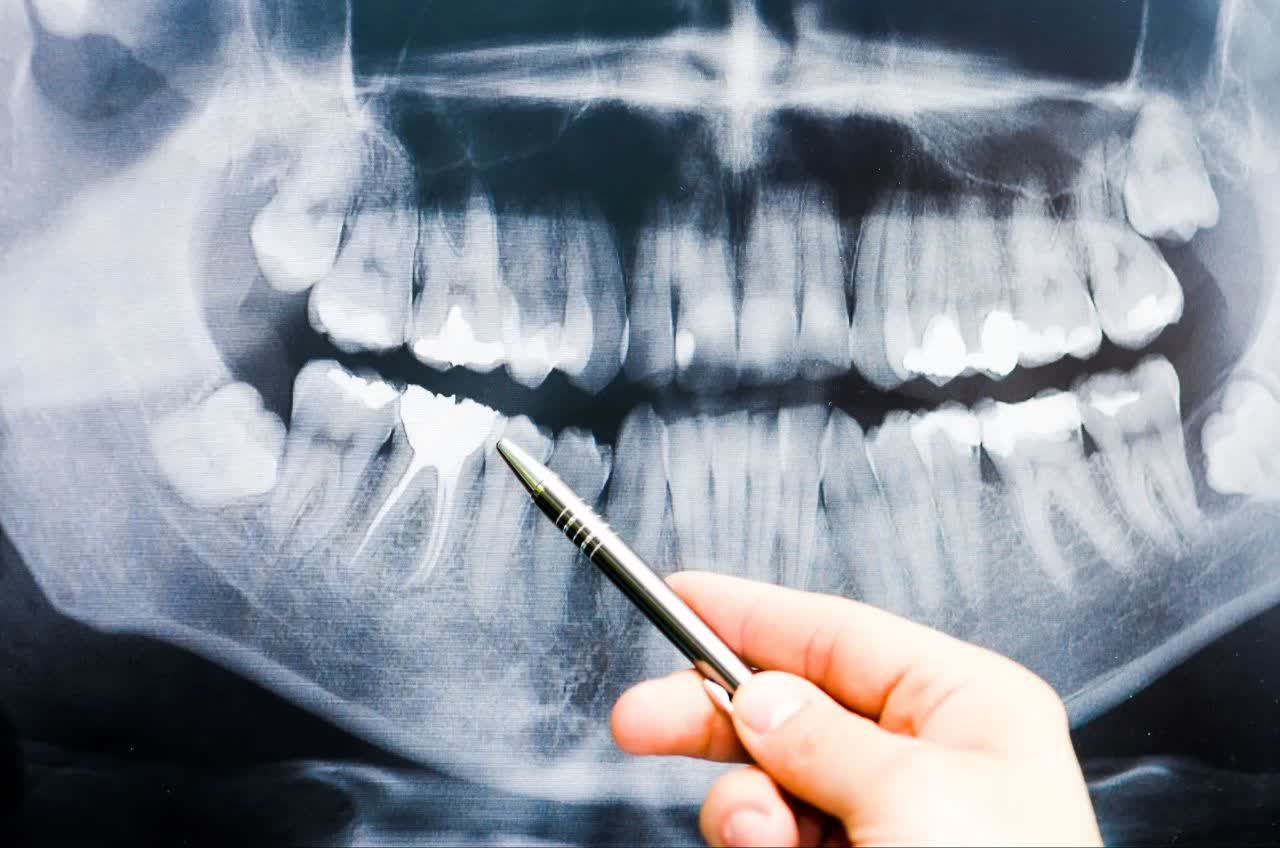

رادیوگرافی پانورامیک دندان (OPG)

رادیوگرافی پانورامیک یا OPG (Orthopantomogram) یکی از روشهای پیشرفته تصویربرداری در دندانپزشکی و فک و صورت است که امکان مشاهدهی جامع دندانها، فک بالا و پایین، مفصل گیجگاهی-فکی (TMJ) و ساختارهای اطراف را در یک تصویر فراهم میآورد. این روش، سریع، بدون درد و با دوز پایین اشعه انجام میشود و به دلیل پوشش وسیع و دقت بالا، یکی از اصلیترین ابزارهای تشخیصی محسوب میگردد.

بررسی و تشخیص دندانهای نهفته (مانند دندان عقل)

ارزیابی پوسیدگیهای بیندندانی و ضایعات اطراف ریشه

تشخیص کیستها، تومورها و بیماریهای فکی

بررسی شکستگیها و آسیبهای استخوان فک

طرحریزی درمانهای ارتودنسی و بررسی موقعیت دندانها

بررسی وضعیت سینوسهای فکی

برنامهریزی جراحیهای دهان و کاشت ایمپلنت